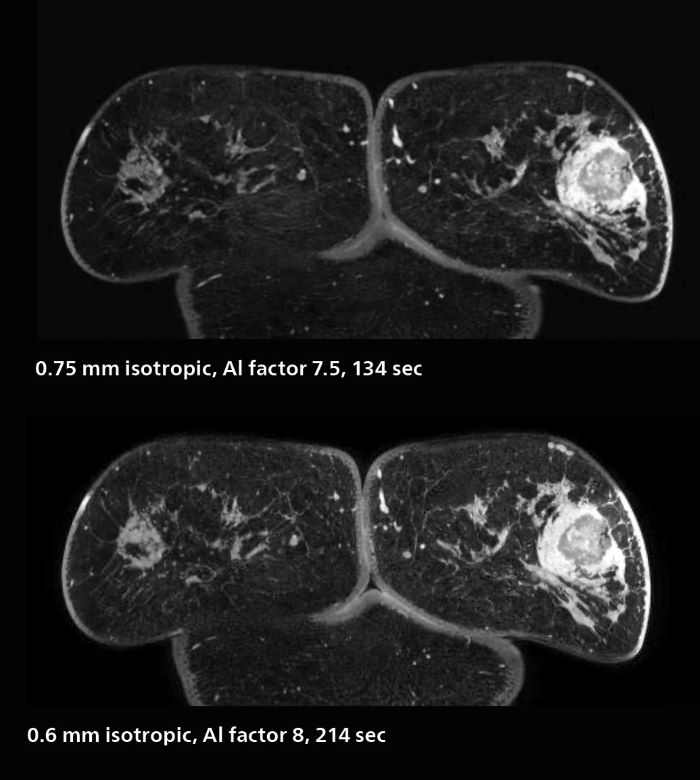

Fast, dynamic breast imaging for diagnostic confidence

Speed and high image quality are also important factors determining the diagnostic value of breast MRI. “When the spatial resolution is not high enough for making the diagnosis of breast cancer, a very difficult decision must be made,” says Dr. Katahira. “Since SmartSpeed now allows us to increase the resolution, we can often easily provide a confident answer. In the past with SENSE we used 1.2 mm isotropic voxels in breast imaging after contrast admission. With Compressed SENSE that is 0.8 mm. Now with SmartSpeed we can acquire 0.6 mm isotropic voxels and the images are so clear that even tiny details are clearly visible.” “For example, we can now scan 20 consecutive, very fast dynamic images of the mammary glands with a single 3-second volume acquisition. This allows us to see how the blood flow is progressing in a very different way.” “The use of SmartSpeed has considerably improved our breast cancer imaging, with higher temporal resolution, higher spatial resolution, and higher SNR compared to the past, when we were using just Compressed SENSE. In addition, the dynamic study is now more useful in diagnosis because the ultrafast dynamic scan can be taken every 3 seconds.”

3D MRI of breast cancer

Scanning was performed with two different voxel sizes. AI enabled volume MRI allows image reconstruction in other directions. Biopsy revealed invasive ductal carcinoma in this patient. Performed on Elition X.

The hospital’s routine ExamCards for breast imaging include: